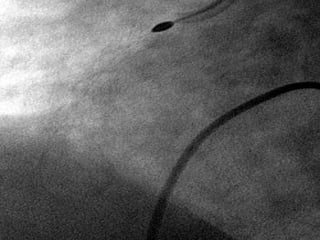

Angioplastía Percutánea